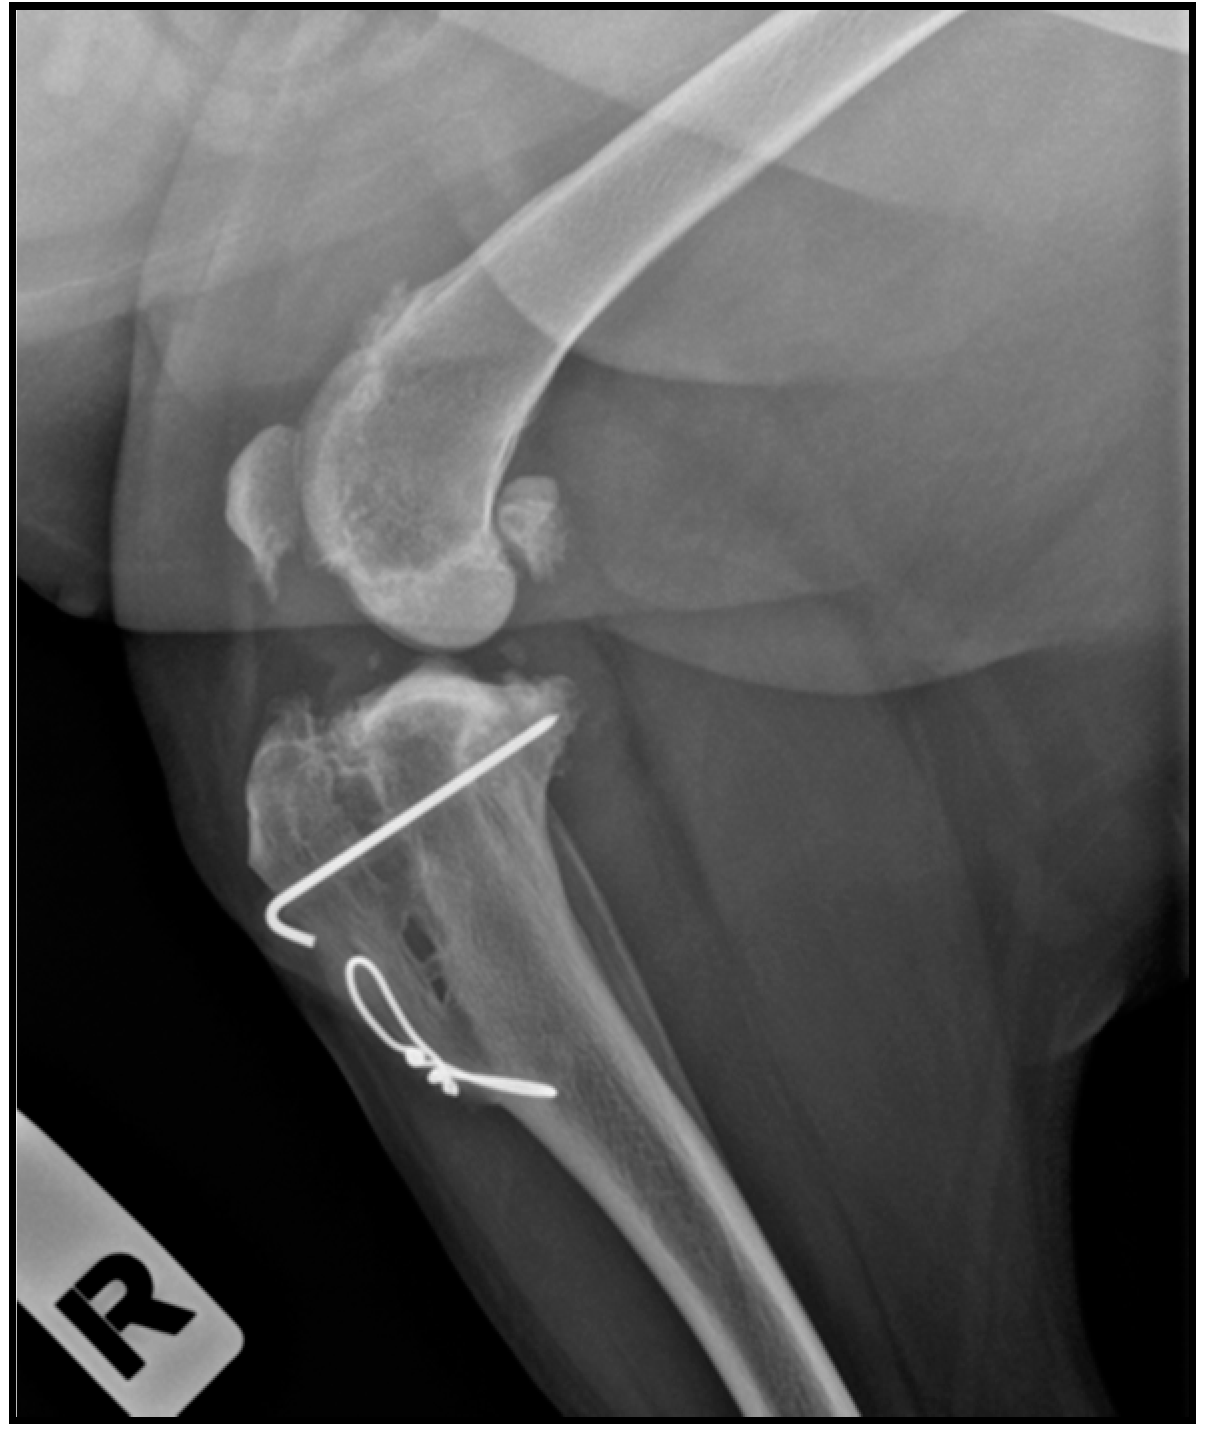

2.4. Radiographic Assessment

- Valiño-Cultelli, V.; Varela-López, Ó.; González-Cantalapiedra, A. Preliminary Clinical and Radiographic Evaluation of a Novel Resorbable Implant of Polylactic Acid (PLA) for Tibial Tuberosity Advancement (TTA) by Modified Maquet Technique (MMT). Animals 2021, 11, 1271. [Google Scholar] [CrossRef]